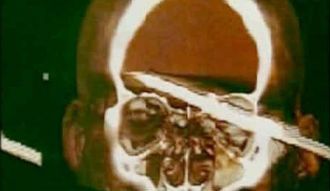

Pescador se clava un arpón en la cabeza por accidente y sobrevive

Emerson de Oliveira Abreu estaba pescando en las costas de Río de

Janeiro, Brasil, cuando

de repente el arpón que disparó rebotó contra unas rocas y

entró en su cabeza, según publicó el sitio británico

The Sun. Abreu tuvo que ser trasladado de inmediato a un

hospital, donde los médicos lo operaron durante 5 horas

para recuperar el objeto punzante.

“Es un milagro”, aseguró a los medios el padre de Abreu, Edilson. El

arpón medía unos 15 centímetros, pero no dejó rastro de su paso

porque no comprometió las zonas más delicadas del cerebro.

Los amigos del pescador declararon que se había metido por arriba

del ojo izquierdo y casi había entrado en su totalidad

dentro de la cabeza del hombre